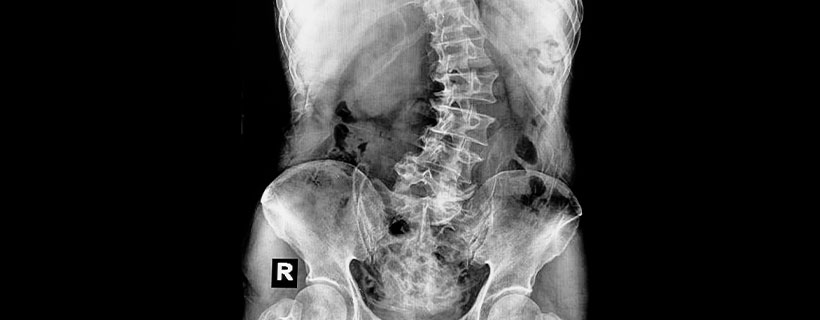

As someone with scoliosis, we are sure you know how much it can interfere with daily tasks such as standing, sitting, walking, or even breathing. Finding relief from scoliosis can be a daunting journey with limited treatment options.

Living with scoliosis can have a tremendous impact on your life, from your emotional state to your ability to perform mundane tasks. Scoliosis is one condition that should be actively managed, or it may worsen if left untreated.